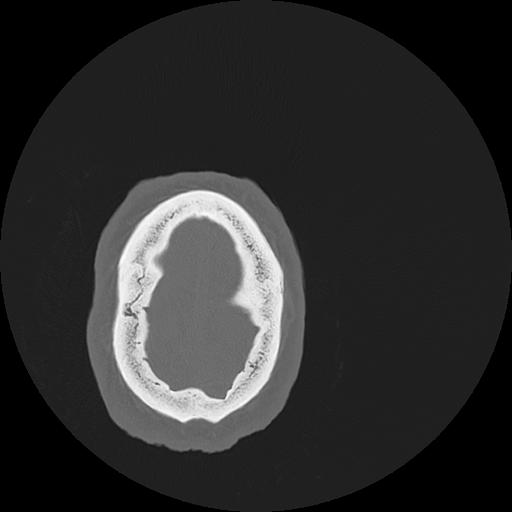

7 HUESO,,Vol,0.5,HUESO,,